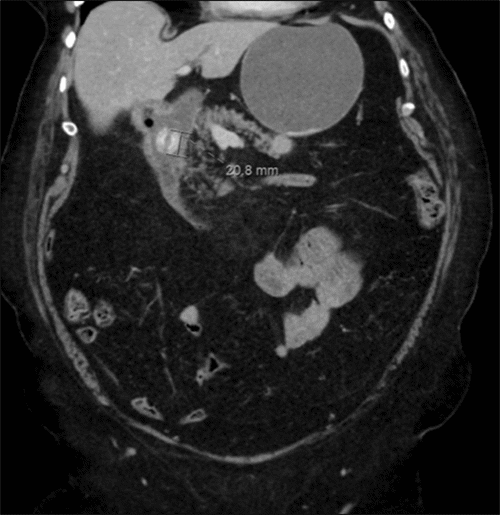

A computed tomography (CT) scan demonstrated a 2 cm rounded, radiopaque structure within the second portion of the duodenum, obstructing the outflow of stomach contents. The stomach appeared moderately dilated. The gallbladder was not clearly visualized, suggesting inflammation with erosion into the duodenum, stomach, or hepatic flexure. The majority of gallstone impaction sites are in the ileum related to the smaller diameter of the distal small bowel. Mild intrahepatic biliary ductal dilation, most significant in the left hepatic lobe, was observed (Figures 1 and 2).

Figure 1. Coronal CT Imaging of Gallstone Ileus. Published with Permission

Coronal CT image demonstrating a gallstone within a small bowel loop in the right upper quadrant, with no evidence of distal small bowel dilation